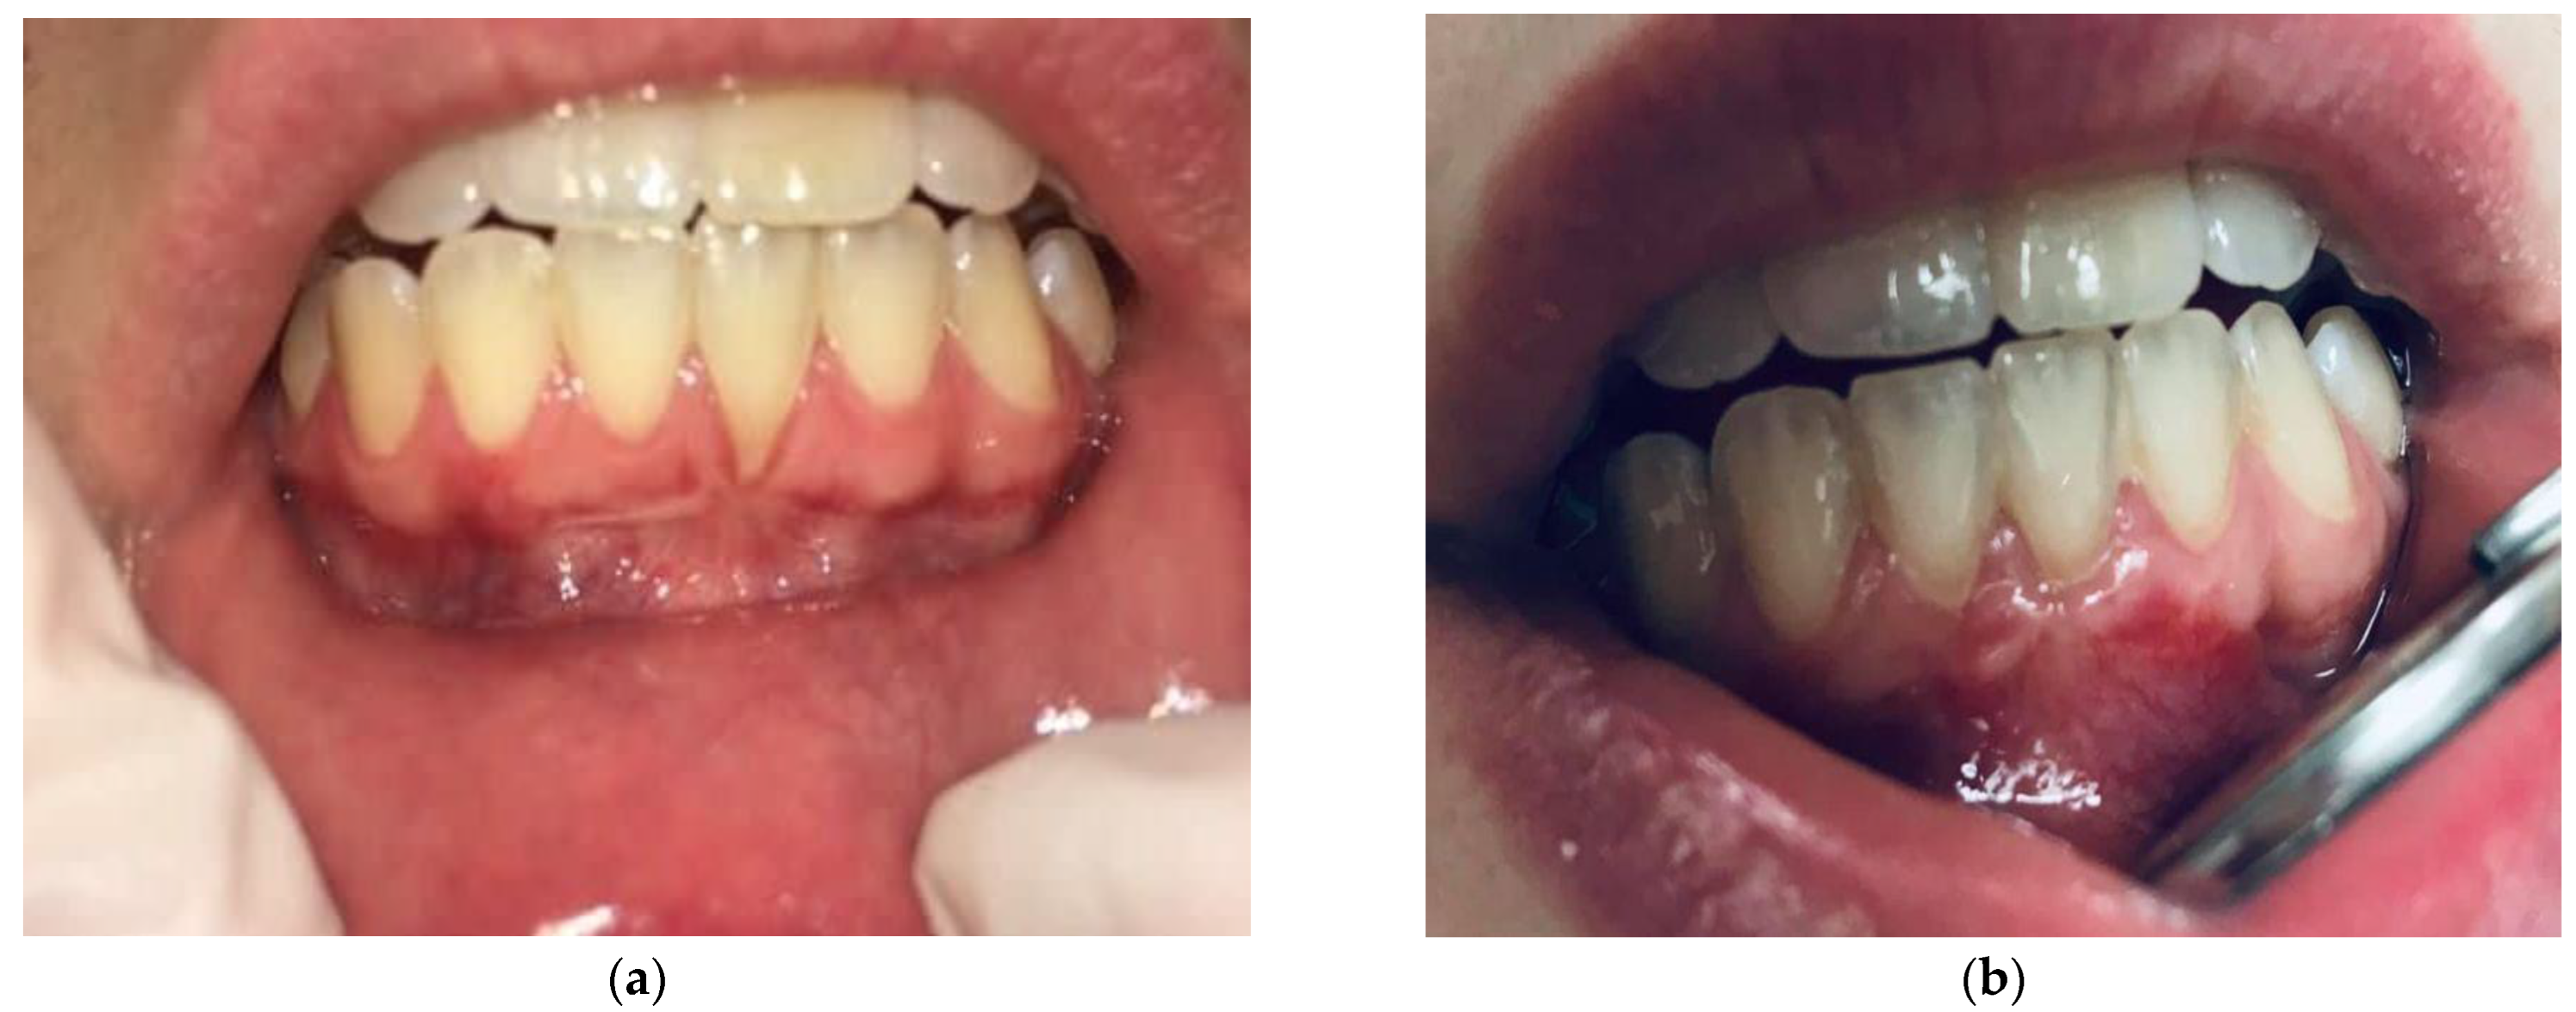

2.1.4. Surgical Procedures

2.2. Post-Surgical Protocol